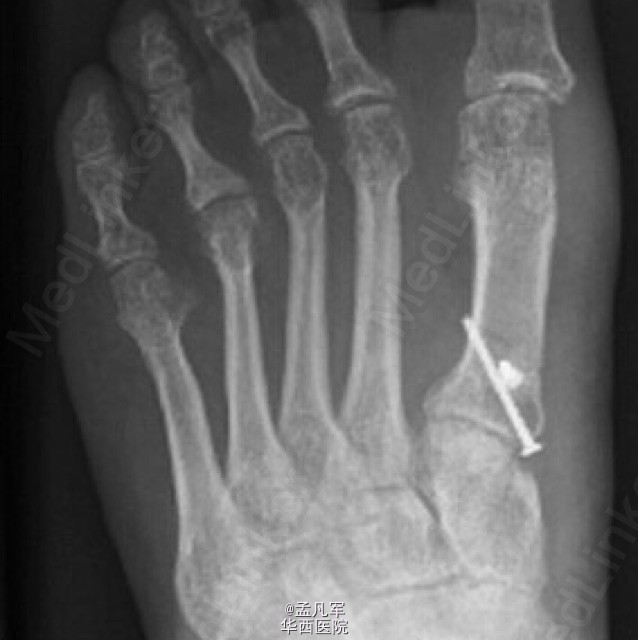

拇外翻是导致成人和青少年足部疼痛和畸形的常见原因。对不伴有严重脱位和关节炎的跖骨远端关节角异常合并跖骨近端关节面固有角增大的中、重度拇外翻畸形,第一跖骨近端截骨术或跖跗关节融合术可以有效纠正拇外翻畸形。 近端 V 形截骨术是一种常见的手术方式,可以有效的纠正角度和提高 AOFAS 评分。近端 V 形截骨术由 Sammarco 在 1929 年首次进行描述,近些年,一些学者提出应将近端 V 形截骨术联合螺钉固定与其他近端截骨方式进行对比。因为,近端 V 形截骨术在操作上存在一定的难度,并且存在一定程度的失败率。 而第一跖骨楔形截骨术可以在截骨后可以进行定制钢板固定,在稳定效果上可以更胜一寿。其操作性较 V 形截骨术更为简单。为了验证第一跖骨近端楔形截骨术与 V 形截骨术在治疗拇外翻的效果,目前 Mark 等人采取前瞻性的随机对照研究,将两者的最新研究结果发表于近期的 JBJS。该研究结果显示,在对于患者的临床结果评估上,这两种方法没有显著差异。此外,还发现第一跖骨楔形截骨术可以延长第一跖骨的长度,而 V 形截骨术正好相反,会影响第一跖骨出现短缩。跖骨近端楔形截骨术,术后跖间角从术前 14.8°±3.2°改变至术后 9.1°±2.9°(P<0.05),而 V 形截骨术使跖间角从术前 14.6°±3.9 改变至术后 11.3°±4.0°(P<0.05)。手术过程所需时间,两者相似楔形截骨术需 67.1±16.5 分钟,V 形截骨术需要花费 69.9±18.6 分钟(P=0.51)。 最终该研究者认为跖骨近端楔形截骨术与 V 形截骨术在影像学结果和术后患者疼痛、满意度以及功能上都具有可比性。值得注意的是两个截骨术,对于患肢的长度结果存在差异。因楔形截骨术在操作技术上,相对较为简单,所以临床医生采用率相对高。